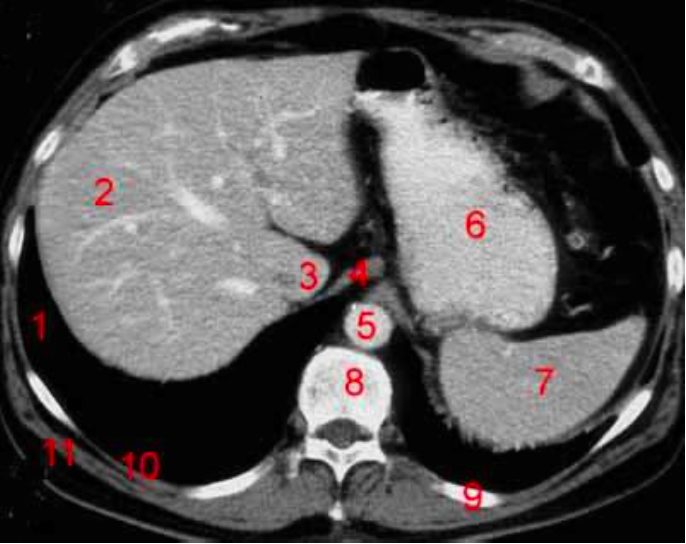

Number 2?

Rt lobe of liver

Number 4?

Rt diaghragmatic crus

Rt lobe liver

Number 1?

R lung

Number 6?

Stomach

Number 8?

Body of thoracic vertebra

Number 9?

Lt rib